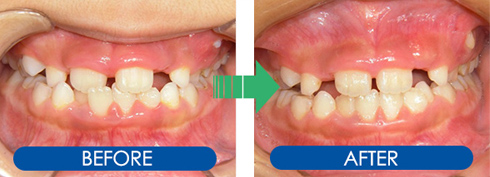

矯正治療のビフォーアフター

頑張って取り組んでいただいた子ども達の症例をご覧ください!

叢生症例1